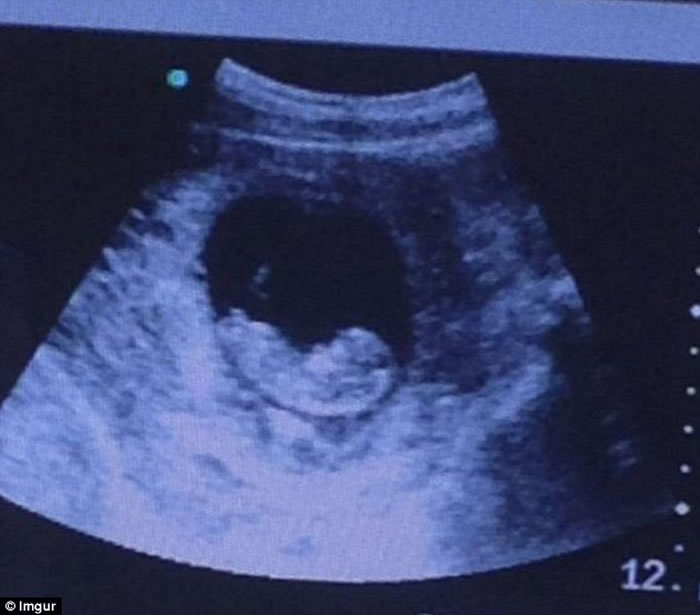

(神秘的地球报道)大多人看到胎儿超声波图,都会感到窝心,期待新生命的诞生。然而,外国有人上载一张超声波图,却令不少网民毛骨悚然。

一名网民上载友人胎儿的超声波图,可以看到胚胎正在子宫中孕育,但当望向图的右方,不少人均惊呼:“没有人看到魔鬼吗?”原来,右方的阴影似足一张脸孔,虽然有人说像魔鬼,但亦有人觉得是美人鱼,甚至是印度女神。

照片吸引了逾50万人次观看,网民都对“脸孔”议论纷纷。